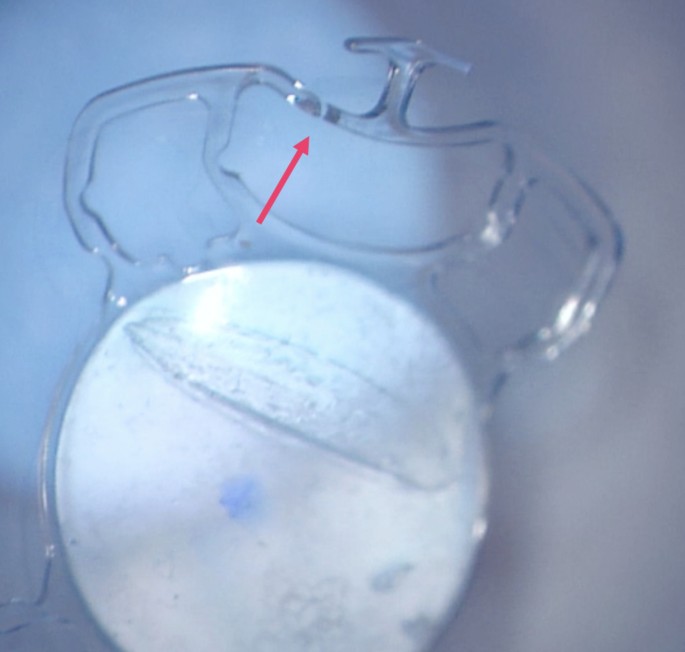

For the creation of the tunnels, a 3.5 × 3.5 mm partial thickness scleral flap was sculped with a crescent knife up to the limbus. A 25-G needle was used to perforate the deep scleral lamella bed at 1.5 mm distance from the limbus (Fig. 2). Consecutively, a 25G crocodile forceps was used to grasp the specialized IOL at the proximal T-shaped harpoon haptic (HH) and externalize it through the scleral tunnel (Fig. 3). The scleral flaps were sutured with a 10 − 0 Nylon suture. One finding during the performance of the HH technique was that some breakage points in the material became apparent. In two IOLs, at the moment of externalisation with the crocodile forceps, one arm of the harpoon haptics toreoff (Fig. 4). In another case, the bridge of the IOL got separated (Fig. 5). Those three attempts were not included in the analysis.